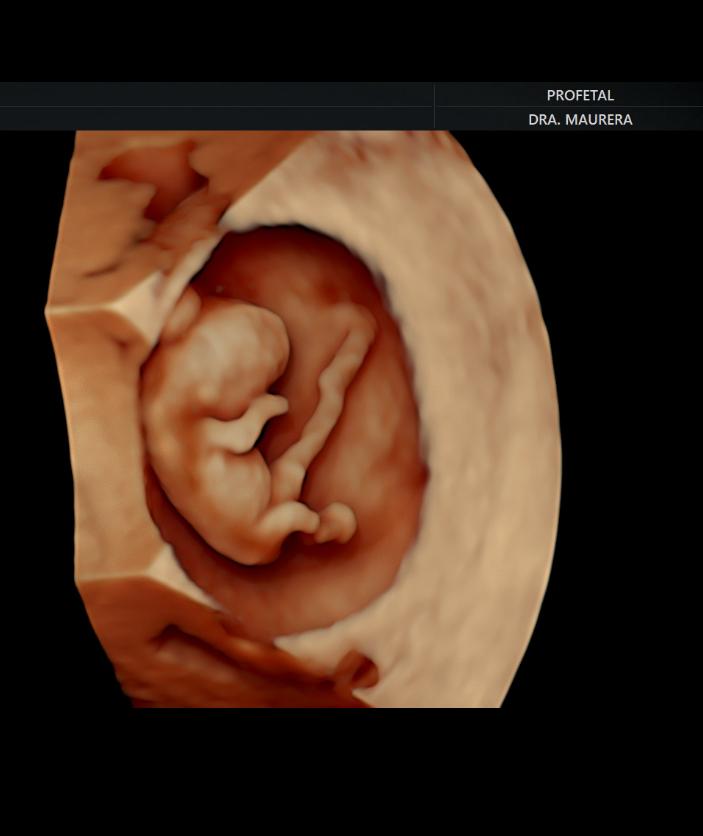

• Ecografía de Viabilidad (Semanas 4-11): Un examen transvaginal para confirmar la progresión normal del embarazo y el número de embriones. Es crucial para mujeres con sangrado, dolor, o antecedentes de abortos y embarazos ectópicos.